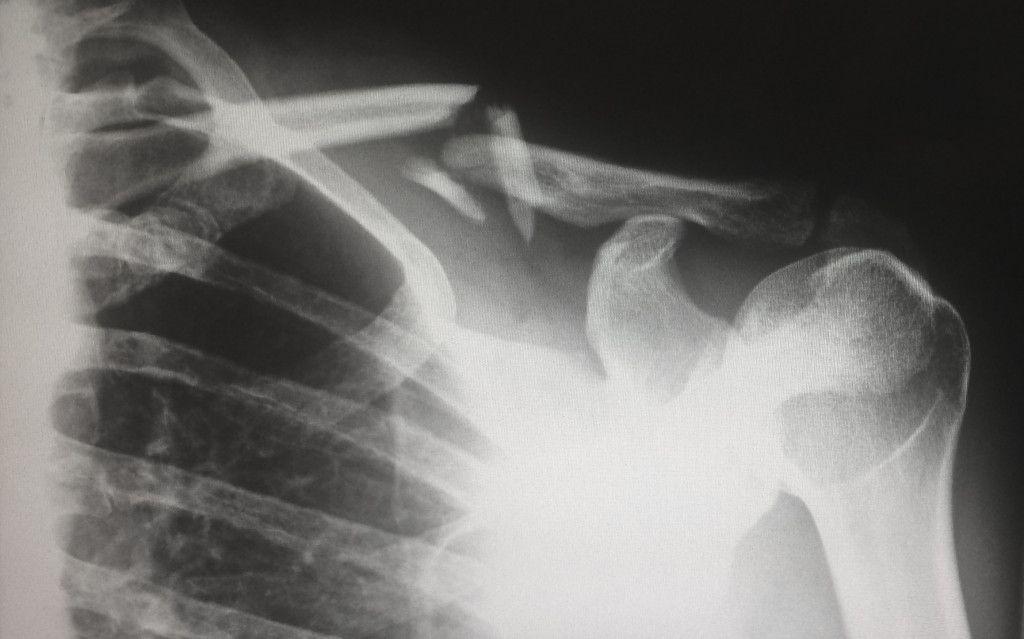

Osteoporóza: Existuje postup, jak se před touto nemocí účinně chránit

Vznik osteoporózy mohou způsobit i poruchy příjmu potravy